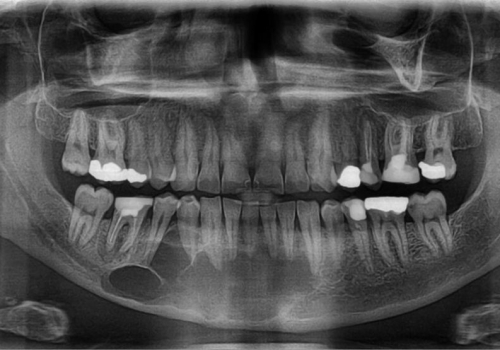

İnkşafı və böyüməsi tədricən baş verdiyindən, bu proses pasiyent tərəfindən demək olar ki hiss edilmir. Yalnız törəmənin ciddi ölçülərə çatması nəticəsində və ya iltihablanması nəticəsində meydana çıxan kliniki əlamətlər nəticəsində aşkarlanır. Əksər hallarda isə çəkilən diş və çənə rentgen şəkillərində təsadüfən rast gəlinir.